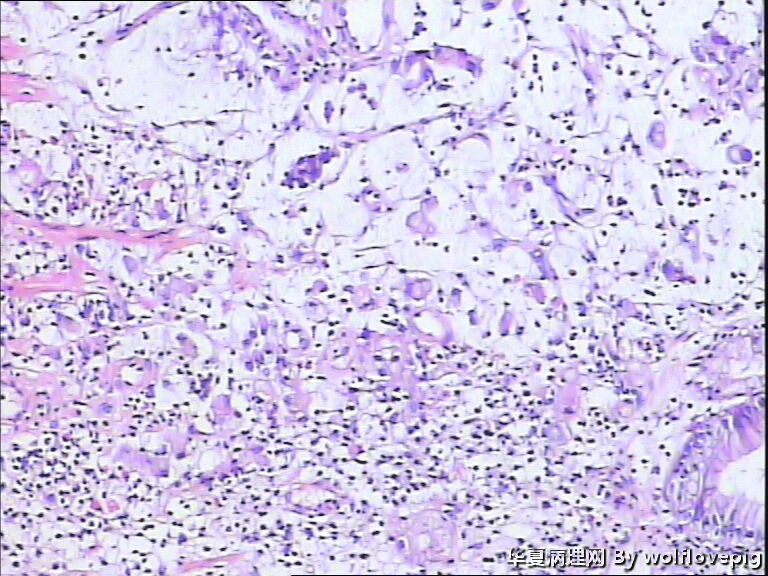

男,60y,胃窦呈结节样改变。

• 请教!胃镜活检。图1

图1

印戒细胞癌

胃印戒细胞癌

低分化腺癌(含印戒细胞癌)

粘液腺癌,部分呈印戒细胞癌。

黏液腺癌。

肿瘤中含有50%的细胞外黏液池,黏液中漂浮着散在或串珠状的癌细胞,癌细胞为富含黏液的柱状细胞及印戒细胞。

粘液腺癌,倾向于印戒细胞癌

粘液腺癌

黏液腺癌为主,部分呈印戒细胞癌